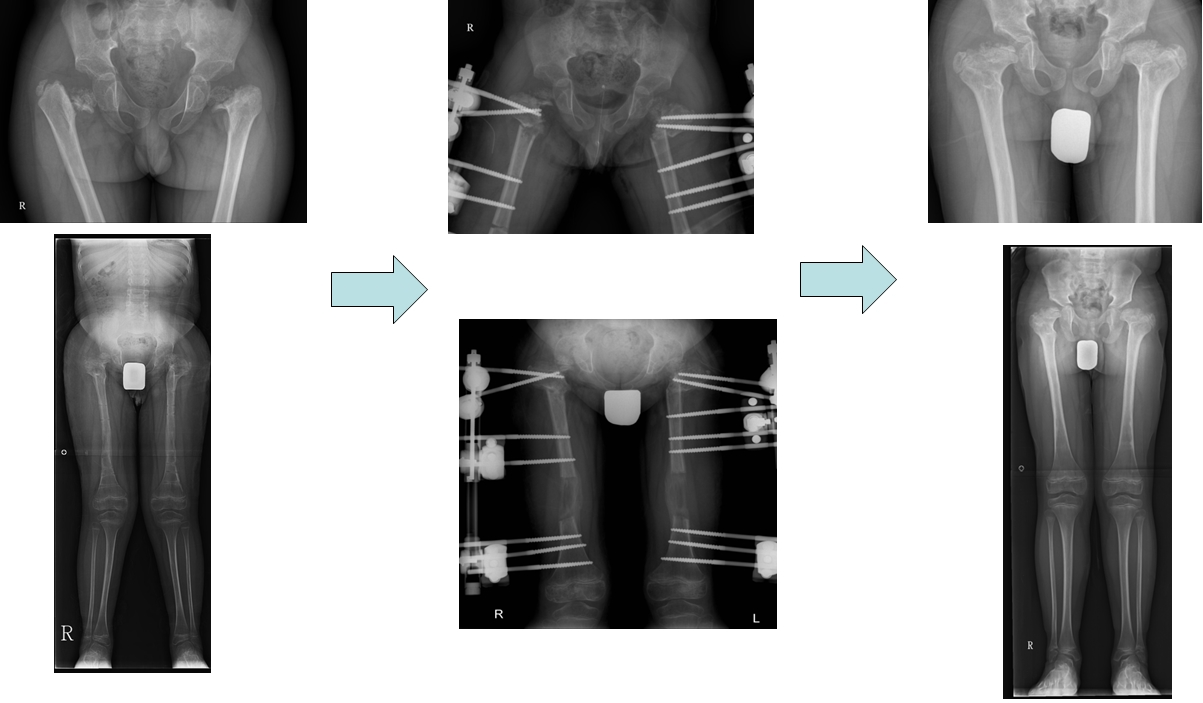

공지 척추골단이형성증환자의 고관절교정 및 대퇴골연장

척추골단이형성증으로 허벅지뼈머리가 변형되고 하지길이가 짧아 교정술과 연장술을 시행하였습니다.

Perform correction surgery and elongation to treat abnormal femoral head and short limbs caused by spondyloepiphyseal dysplasia.